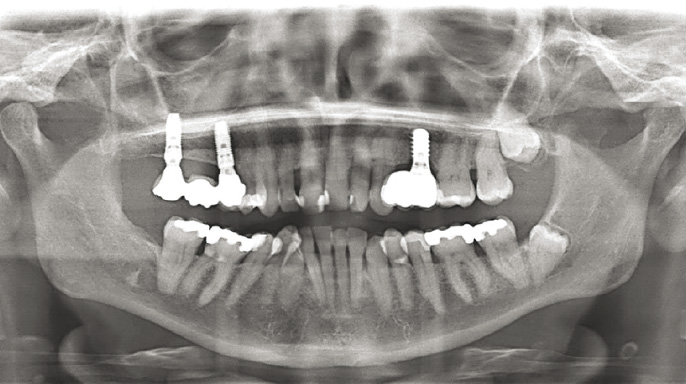

Moderní stomatologie prochází technologickou revolucí, kterou pohání integrace pokročilých digitálních nástrojů v diagnostice, plánování a léčbě. Mezi nimi se počítačem řízená implantologie stala základním pilířem, zejména u složitých výkonů, jako jsou estetické rekonstrukce a celková rehabilitace čelistního oblouku.

Digitální pracovní postupy ve stomatologii přinesly revoluci v přístupu odborníků ke složitým zákrokům – zlepšují přesnost, efektivitu a dosažené klinické výsledky. Mezi digitálními inovacemi se výrazně prosazují systémy pro plnou navigaci...

Použití pasivní a aktivní navigace při implantaci umožňuje dosáhnout relativně přesné pozice, hloubky i angulace štoly pro implantát, a tím pádem dobrou prediktabilitu protetického ošetření. Zejména používání operačních šablon pro pasivní navigaci…